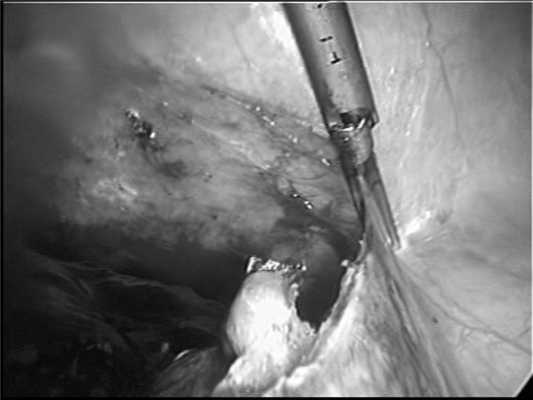

В первую очередь с помощью биполярной коагуляции или ультразвуковых ножниц Ultracision (см. рисунок, а) Рисунок 1. Этапы лапароскопической спленэктомии. а - пересечение связочного аппарата селезенки с помощью ультразвуковых ножниц Ultracision. пересекали селезеночно-ободочную и селезеночно-желудочную связки.

Далее визуализировалась поджелудочно-селезеночная связка с проходящими в ней артерией и веной, при этом хорошо определялись хвост поджелудочной железы и ворота селезенки. При выполнении первых двух операций ножку селезенки обрабатывали сшивающим аппаратом Endo GIA 60 (высота скрепки 2,5 мм) и с дополнительным наложением гемостатических Z-образных швов (см. рисунок, б). Рисунок 1. Этапы лапароскопической спленэктомии. б - пересечение ножки селезенки сшивающим аппаратом.

В дальнейшем, в 7 наблюдениях использовали аппарат Ligasure, что было достаточно для надежного гемостаза (см. рисунок, в). Рисунок 1. Этапы лапароскопической спленэктомии. в - пересечение ножки селезенки с помощью аппарата Ligasure.